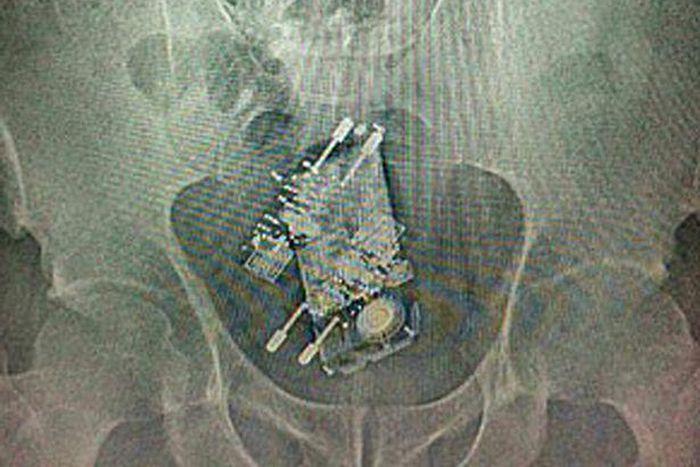

X-ray of prison inmate who attempts to smuggle phone and two chargers by swallowing them

X-rays showed up the objects inside his stomach as he passed through security on his way back into Papuda Prison in Brazil.

The phone and chargers had been wrapped in plastic before he swallowed them.